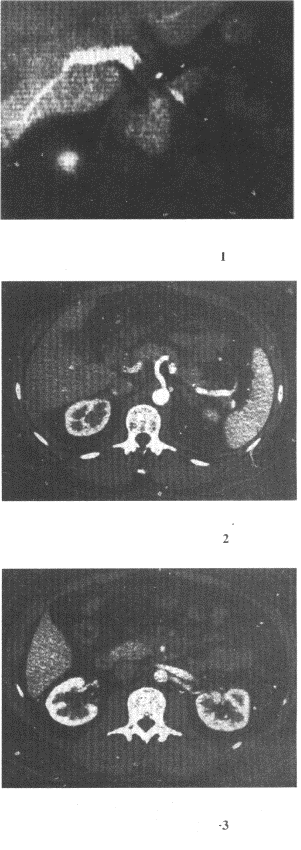

2.男,58歲,進食梗阻感,結合圖像,最可能的診斷為

正確答案:D 解題思路:食管范圍較長的不規則充盈缺損,管腔變窄,伴表面有龕影,結合病史為食管癌性病變。